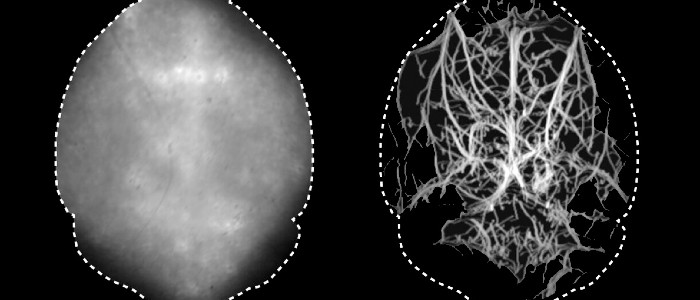

Згідно з дослідженням, опублікованим в четвер в журналі Optica, новий метод усуває все це і створює докладну і динамічну карту судинної мережі мозку, яка, на думку дослідників, може бути цінним медичним інструментом.

Зокрема, Разанскі і його команда вводили мишам флуоресцентні мікрокраплі, які подорожували по їх кровоносній системі, і використовували інфрачервоне світло певної довжини, яке може краще проникати в кістки й висвітлювати їх. Ця концепція аналогічна скануванню за допомогою фМРТ, оскільки дозволяє вченим заглядати всередину мозку і бачити, які області активні й коли, за винятком того, що це перший раз, коли вчені змогли зробити це за допомогою флуоресцентної мікроскопії.

«Забезпечення можливості оптичних спостережень з високою роздільною здатністю в глибоких живих тканинах є давню мету в області біомедичної візуалізації», — йдеться в повідомленні Разанскі. «Чудовий дозвіл [цієї техніки] для оптичних спостережень в глибоких тканинах може забезпечити функціональне розуміння мозку, що робить його багатообіцяючою платформою для вивчення нейронної активності, мікроциркуляції, нейросудинної взаємодії й нейродегенерації».